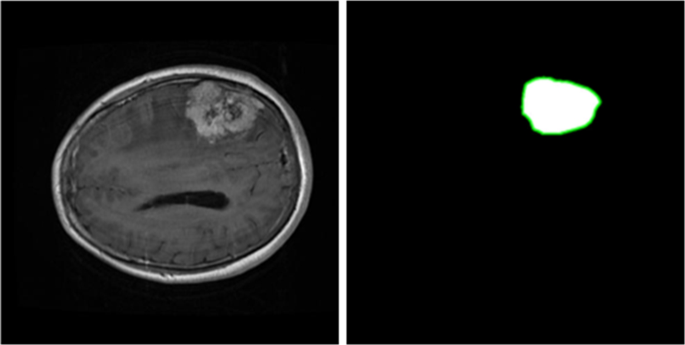

A brain tumor can form in the brain cells (as shown), or it can begin elsewhere and spread to the brain. As the tumor grows, it creates pressure on and changes the function of surrounding brain tissue, which causes signs and symptoms such as headaches, nausea and balance problems.

A brain tumor is a growth of cells in the brain or near it. Brain tumors can happen in the brain tissue. Brain tumors also can happen near the brain tissue. Nearby locations include nerves, the pituitary gland, the pineal gland, and the membranes that cover the surface of the brain.